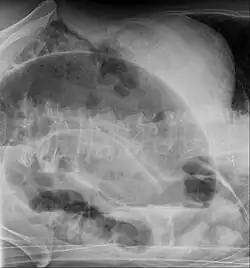

| Radiografia de abdomen mostrando um vôlvulo de sigmoide | |

A clínica é típica de abdômen agudo. O diagnóstico normalmente é feito com Raio-X (parece um balão radiolúcido ou com grãos de café) e tomografia computadorizada.